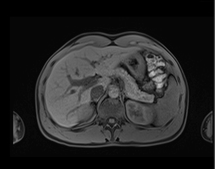

June 4, 2013 — Siemens Healthcare has announced that the U.S. Food and Drug Administration (FDA) recently cleared the company’s CAIPIRINHA (Controlled Aliasing in Volumetric Parallel Imaging Results IN Higher Acceleration) software as part of Siemens’ syngo MR D13A software package for parallel magnetic resonance imaging (MRI). The MRI software helps enable patients with breath-holding difficulties to reduce the amount of time they hold their breath by up to 50 percent without sacrificing imaging resolution or contrast.

Siemens’ CAIPIRINHA software enables acquisition of higher-quality 3-D volumetric interpolated breath-hold sequence (VIBE) T1 images through higher acceleration factors. factors. CAIPIRINHA software is included as standard with Siemens’ D13A software for MAGNETOM Aera 1.5 Tesla, Magnetom Skyra 3.0T, Magnetom Avanto 1.5T, and Magnetom Verio 3.0T systems. It is also available with Siemens’ D14 software for the Magnetom Essenza 1.5T system.